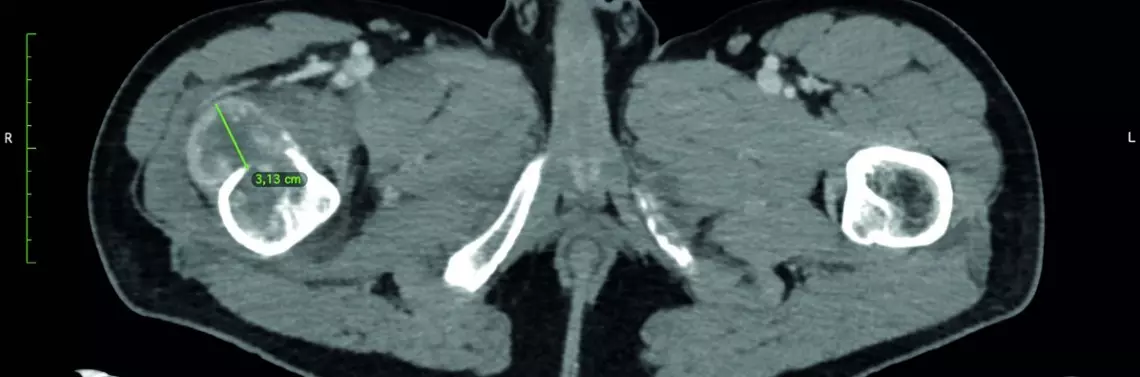

Podczas przygotowania chorego do resekcji przerzutu i implantacji endoprotezy poresekcyjnej u pacjenta wykonano zabieg embolizacji (ryc. 2A i 2B).